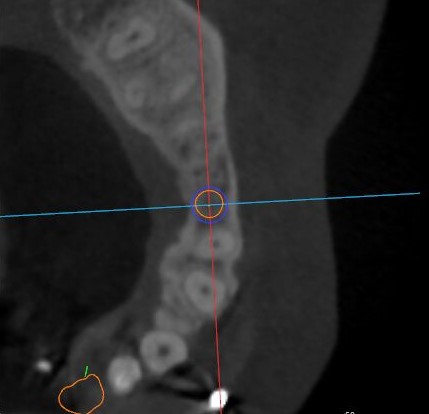

觀察患者CT,可看出患者有上頜竇粘膜囊腫,粘膜囊腫為竇內(nèi)腺體阻塞所致,視情況可有手術(shù)摘除和不予處理兩種方法,此次患者拒絕手術(shù)摘除,故需規(guī)避上頜竇位置。

矢狀面視圖

根據(jù)患者CT顯示,使用種植導(dǎo)航軟件設(shè)術(shù)前手術(shù)方案??紤]到患者拒絕手術(shù)摘除上頜竇囊腫等因素,此次手術(shù)選用了Straumann骨水平4.10*8.0mm的植體,植體末端位點(diǎn)設(shè)計(jì)距上頜竇底壁2mm處的同時(shí)兼顧種植方向和修復(fù)間隙,來(lái)達(dá)到理想的效果。